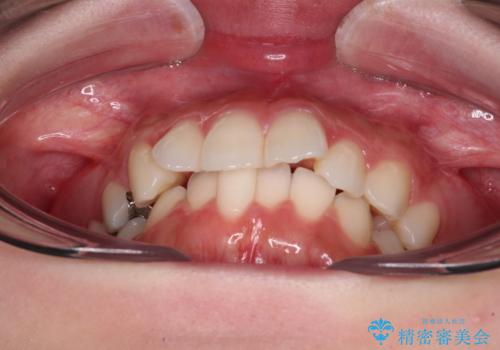

欠損した歯と前に飛び出した前歯 インプラント治療を併用したワイヤー矯正治療

- 上の前歯が下唇に当たる感覚と奥歯の欠損を気にして来院された患者様です。

上顎前歯の突出感は、上顎全体が前方に位置していることが原因であったため、補助装置により上顎全体を後方に移動させることとしました。